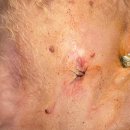

• 여울동물병원 | 신봉동 동물병원에서 강아지 얼굴 종괴 치료받은 후기글

느낌은 없었거든요. ​ 그래서 더 애매했던 것 같아요. ​ 좀 지켜보고 고민을 하다가 결국은 정확하게 확인하는 게 낫겠다 싶어서 신봉동 동물병원을 알아보고 방문하게 됐습니다. ​ 신봉동 동물병원에 도착해서 접수하고 아이 상태를 간단히 말씀드렸는데, 처음부터 차분하게 하나씩 확인해 주시는 느낌이 인상적이었어요...